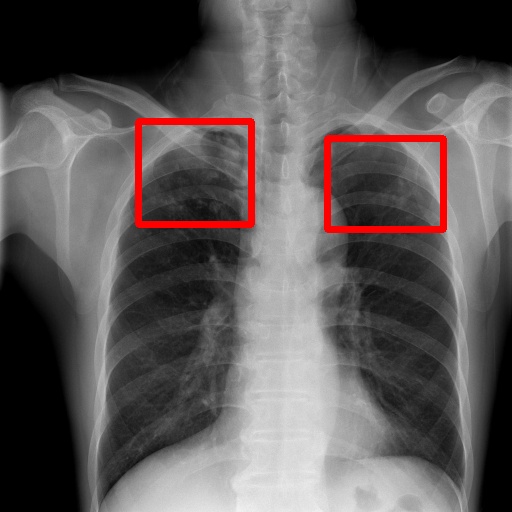

6.4 Visualization

To gain insights into the learning process of deep neural networks on CXR images, we visualize the feature map of SymFormer w/ RetinaNet at a scale of . To achieve this, we employ principal component analysis (PCA) to reduce the channels of the feature map to a single channel. The resulting single-channel map is then converted into a heat map for visualization purposes. The visualization of the learned features, along with the corresponding detection results, are presented in Fig. 6. Upon analysis, we observe that the visualization of healthy cases exhibits irregular feature patterns, indicating the absence of significant abnormalities. In contrast, the visualization of sick but non-TB cases displayed some discernible highlights, potentially representing the presence of lesions. For TB cases, the highlights in the visualization map align well with the annotated TB infection areas, thereby indicating the effectiveness of the proposed SymFormer in learning deep features for TB area detection. Furthermore, in Fig. 7, we offer qualitative comparisons between the proposed SymFormer and the baseline models for TB infection area detection. As evident, SymFormer consistently delivers superior qualitative detection results.